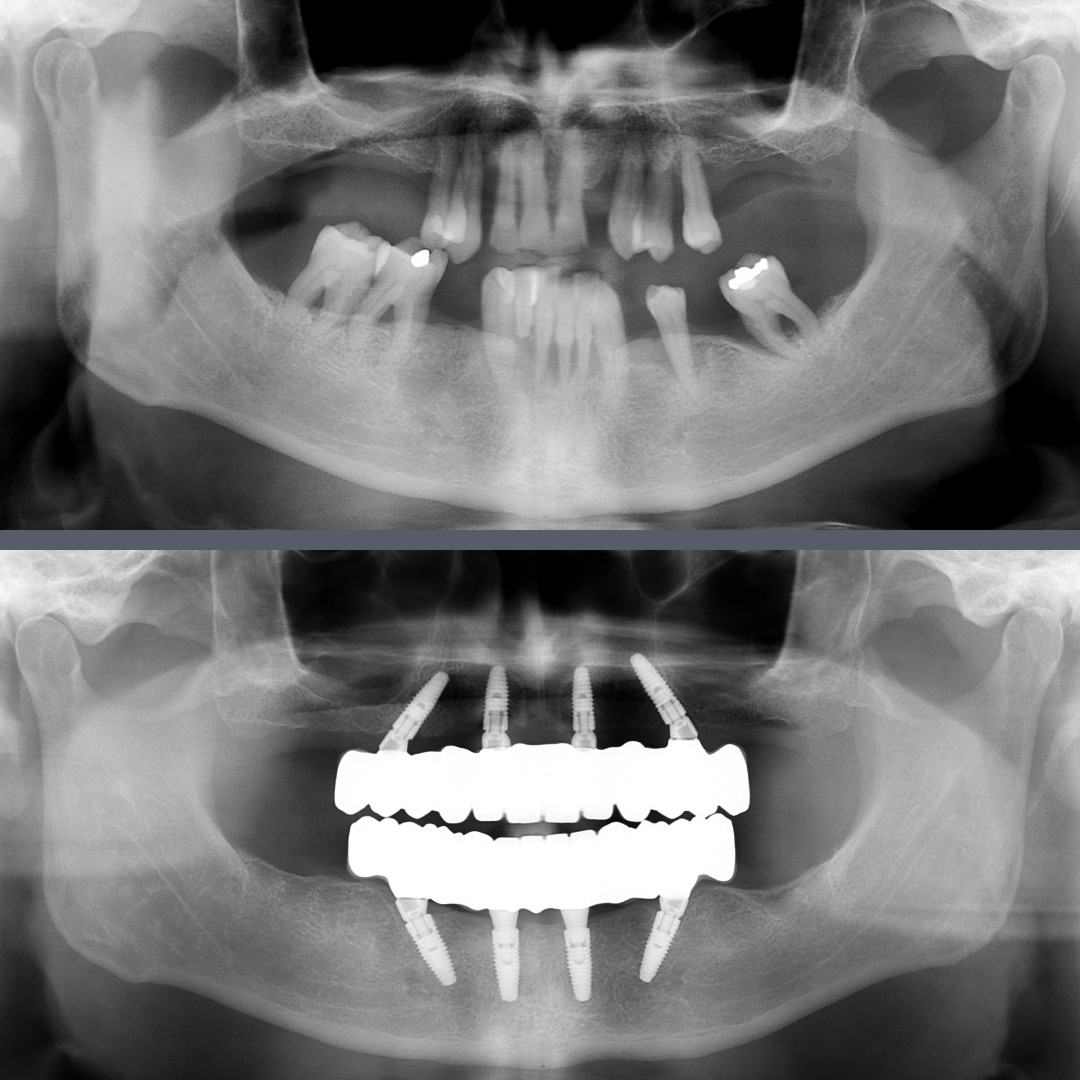

Our 56-year-old patient had been living with advanced periodontal disease (periodontitis) for many years, which had already led to the loss of several teeth. The remaining ones were also severely loose. This resulted in both aesthetic and functional problems, significantly affecting his quality of life.

The patient was looking for a fixed, long-term solution that could be completed as quickly as possible. Fortunately, his bone structure allowed us to place the implants and load them immediately at the time of tooth extraction, so we opted for the All-on-4® implantation method.

After extracting the unsalvageable teeth, we immediately placed four Nobel Biocare implants per jaw. Within 24 hours, a custom-made fixed provisional bridge was fitted. From that point on, his everyday life changed: instead of missing and mobile teeth, he now had stable, full-arch restorations on both the upper and lower jaws.

Once the implants had fully integrated, we proceeded with the final step. Full-arch zirconia bridges were fabricated, precisely adjusted, and securely attached to the implants.